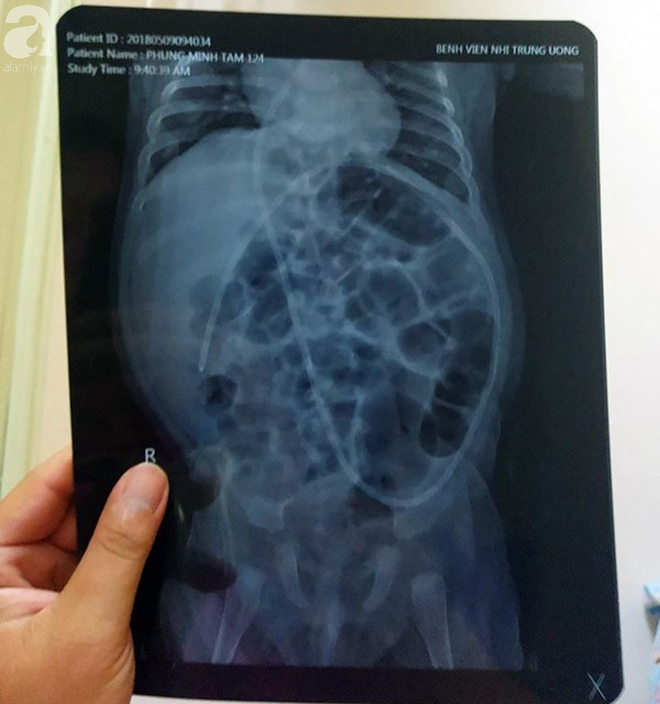

Các bác sĩ phải đặt ống quanh ổ bụng bé.

Sinh được đúng 8 ngày, do tình trạng bệnh của bé Minh Tâm ngày càng chuyển biến xấu nên gia đình đã phải chuyển lên Bệnh viện Nhi Trung ương điều trị. Từ đây, bé Minh Tâm bắt đầu những ngày đớn đau chiến đấu với căn bệnh quái ác…

Tại đây, các Bác sĩ chẩn đoán bé Minh Tâm bị mắc bệnh chậm phát triển, não úng thủy. Tính đến thời điểm hiện tại bé đã phải trải qua 5 lần phẫu thuật để cứu lấy mạng sống.